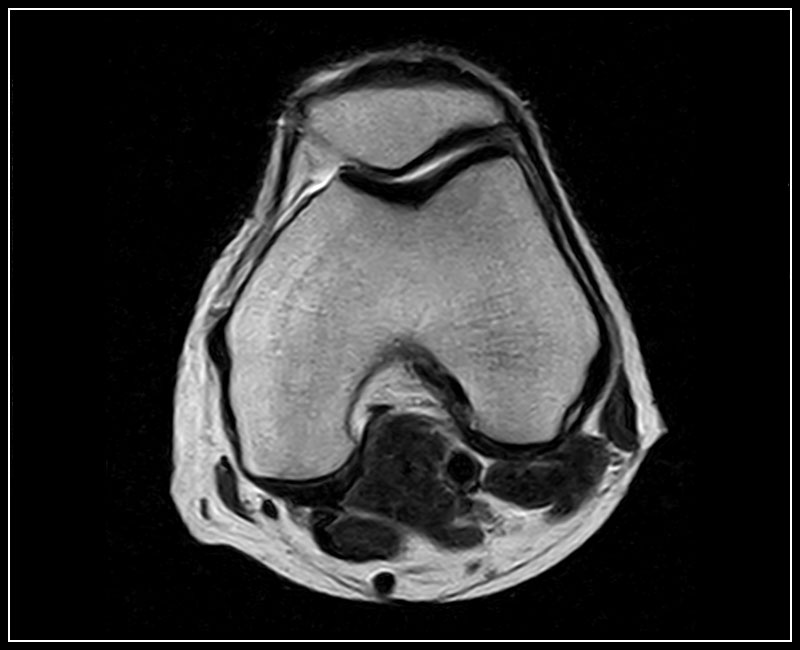

Klinické snímky

Technologie, příslušenství a snímky

G-scan Brio je speciálně navržen pro všechny aplikace pohybového aparátu. Otevřený a naklápěcí design je nový a inovativní způsob provádění MRI, při kterém se poloha pacienta stává nedílnou součástí výsledku vyšetření. G-scan Brio poskytuje pacientovi vysoký komfort s funkcí nejnovějšího zobrazovacího výkonu a sekvencí společnosti Esaote.